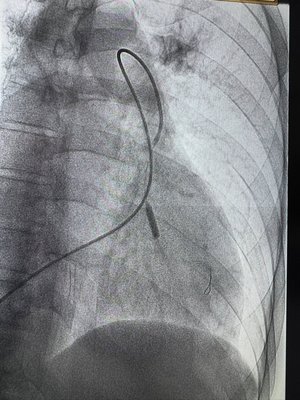

Кардіолог, завідувач відділення кардіології та реперфузійної терапії Центру серця та судин Василь Процько розповів у ФБ, що чоловік страждав на хронічну посттромбоемболічну легеневу гіпертензію — важке захворювання, що проявляється вираженою задишкою та падінням сатурації навіть при мінімальному фізичному навантаженні.

Раніше єдиним шансом для таких пацієнтів була складна відкрита операція — видалення залишків тромбів із легеневих артерій, але в цього пацієнта тромботичні ураження розташовувались надто дистально, тож хірургічне втручання було неможливим.

Єдиним шансом залишалась ендоваскулярна балонна ангіопластика гілок легеневої артерії — сучасна методика, яку рутинно ще не виконують в Україні, були лише певні спроби. Такі операції проводять лише в окремих клініках за кордоном.

І ось — два дні тому ми успішно виконали першу балонну ангіопластику легеневих артерій у нашому центрі!

Ефект перевершив очікування — вдалося суттєво знизити рівень легеневої гіпертензії, пацієнт почувається значно краще, і сьогодні він їде додому." - написав він.

Депутат ЛМР Ігор Зінкевич уточнив, що лікарі 1 ТМО вперше у Львові здійснили унікальну операцію через прокол в судині - ендоваскулярну катетерну балонну ангіопластику легеневої артерії у пацієнта з хронічною посттромбоемболічною легеневою гіпертензією. Ця методика рутинно не проводиться в Україні, а лише в високоспеціалізованих центрах за кордоном.